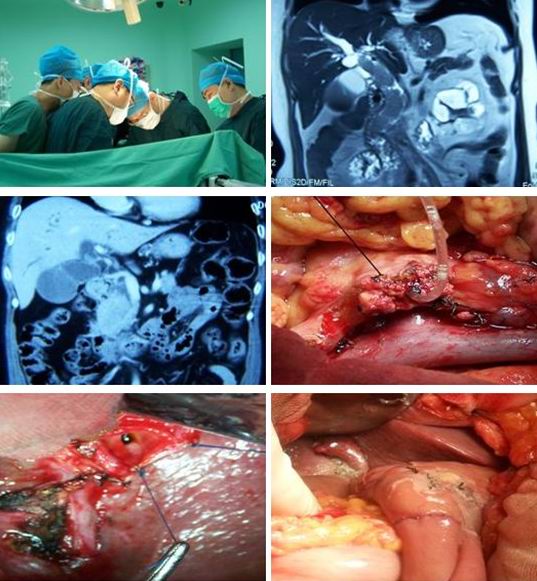

高位膽管癌

肝門區膽管癌後期症狀

肝門區膽管癌

肝門膽管癌晚期死後

肝門膽管癌晚期